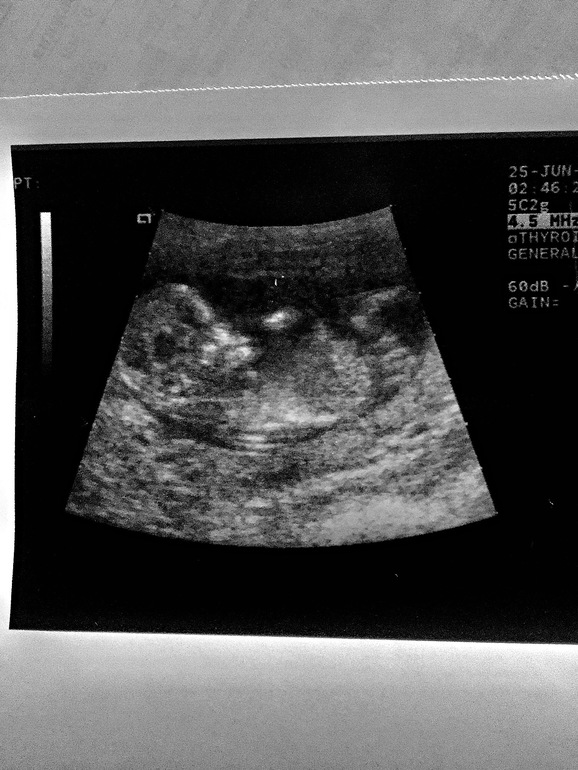

Узи 12-13 недель!!! Мальчик или девочка?

В 12 недель Вам даже опытный узист не скажет, если только наугад. В 16 недель увидете, осталось чуть-чуть.

На этой картинке не понятно

Не видно ничего, только прикрепление пуповины